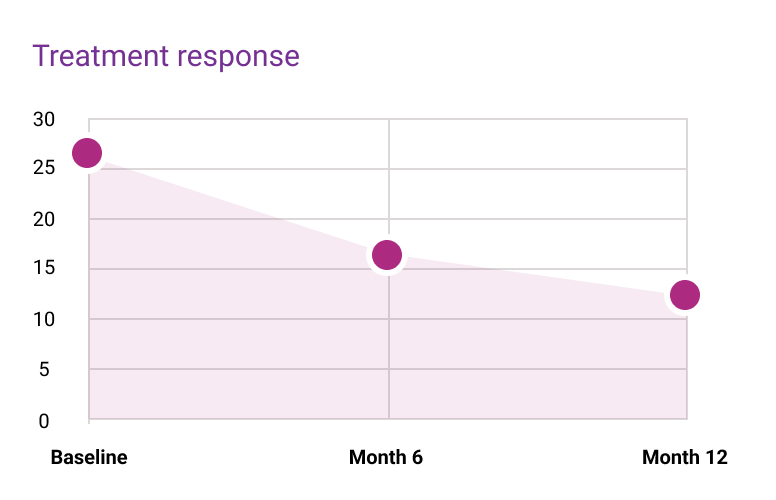

1,6

1,6Donec sollicitudin molestie malesuada. Vivamus magna justo, lacinia eget consectetur sed, convallis at tellus.

1,6